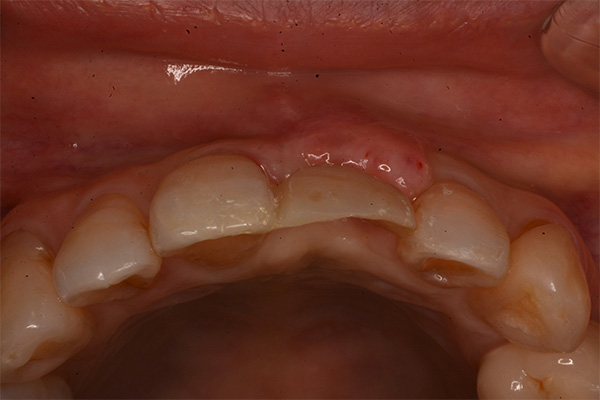

抜歯9ヶ月後(左)歯肉にヘコみができているので手術で歯肉を増大させる

2週間後、赤みは残るが歯肉の厚みは増えた(右)